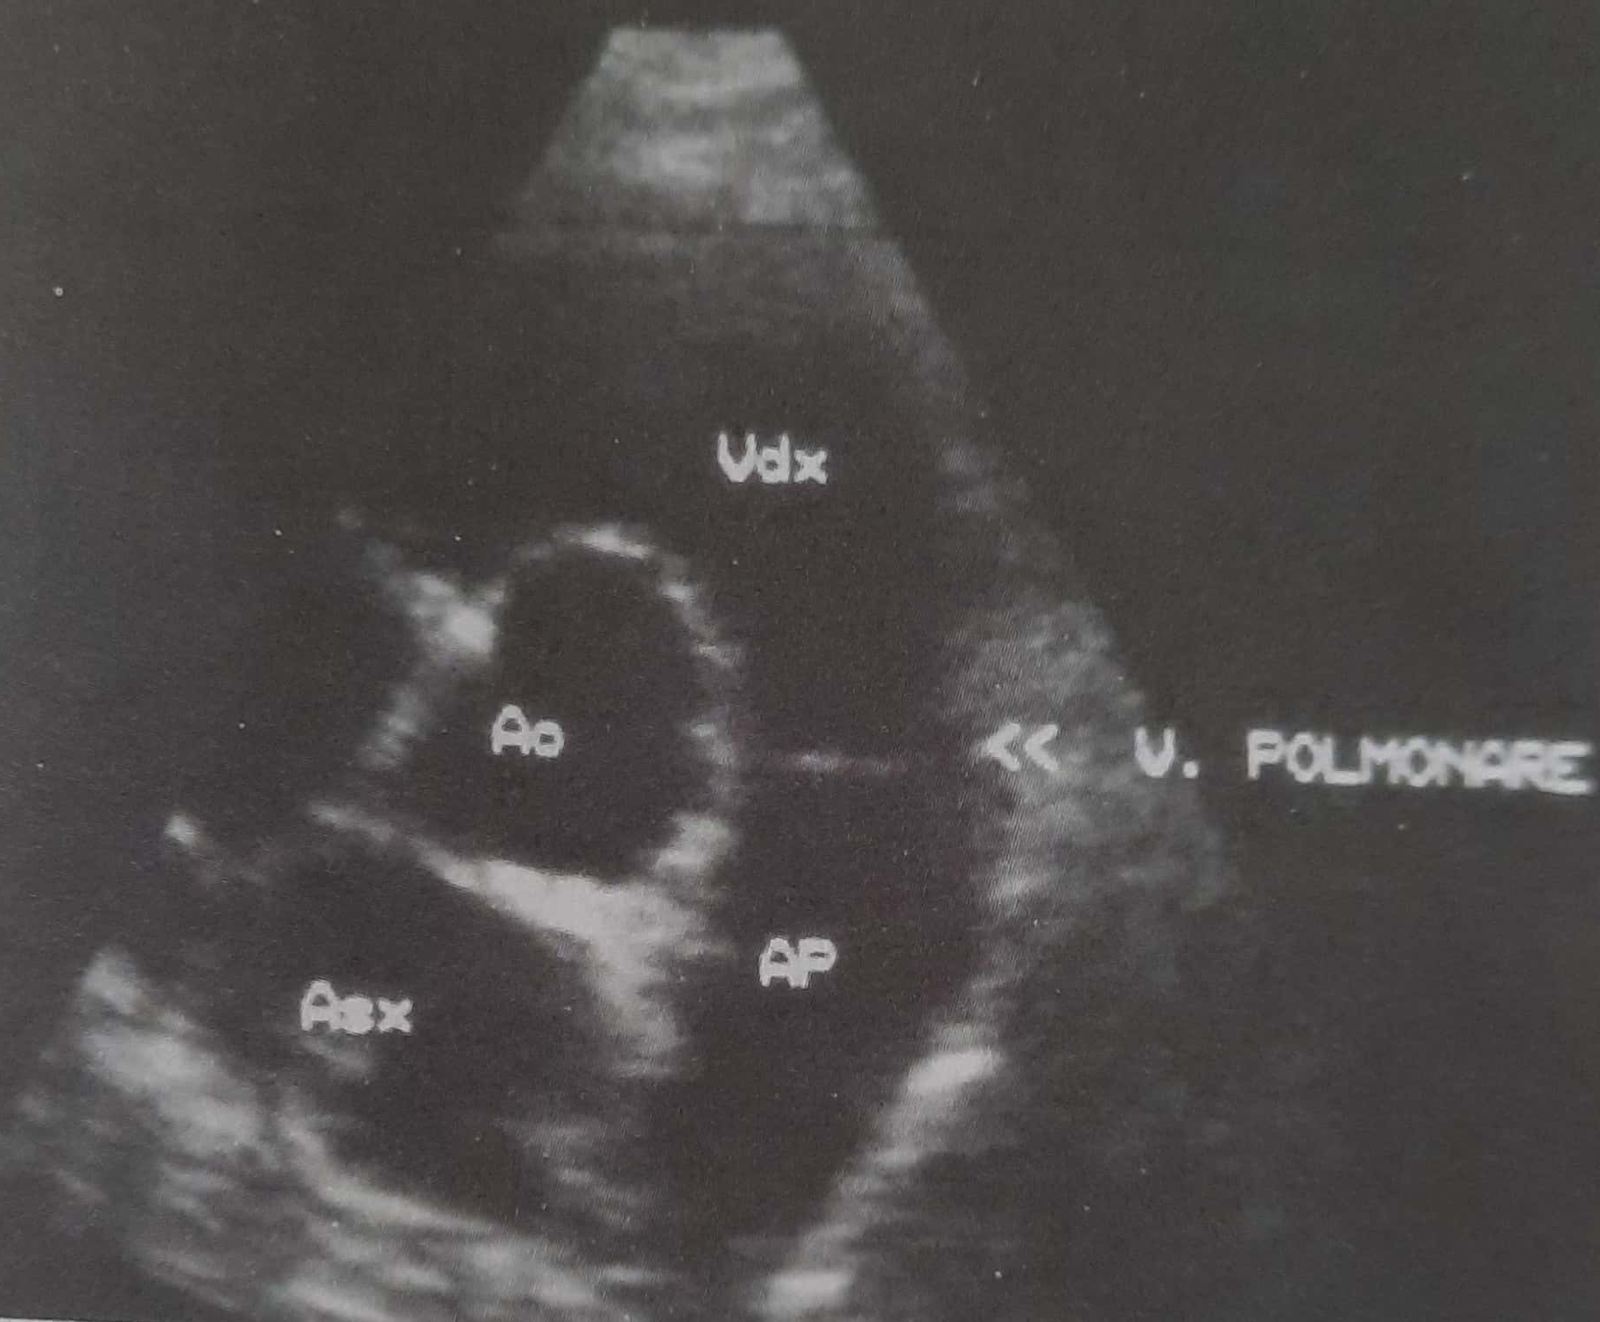

Plani (prerja) i skanimit lehtësisht mbi bazën e zemrës (majtas). Ky seksion siguron vlerësimin ekografik të valvulës pulmunare. AP = arteria pulmonare; Ao = aorta; Asx = atriumi i majtë; Vdx = ventrikuli i djathtë; V. Polmonare = valvula pulmonare.